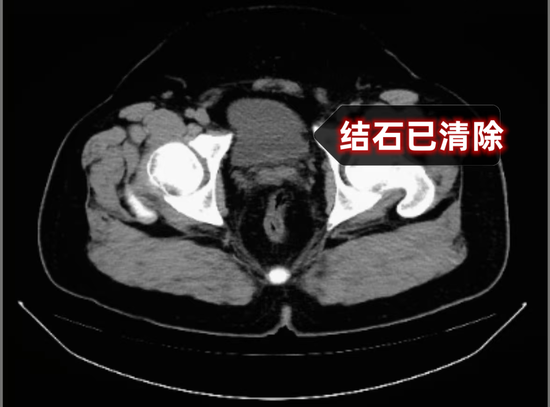

在多学科紧密配合下,手术团队精准定位膀胱内多发结石,利用钬激光将结石逐一击碎并顺利取出,同时精准处理前列腺增生问题,全程操作平稳顺利。术后,在医护团队精心护理与个体化康复指导下,张爷爷尿频、血尿、夜尿频繁等困扰已久的症状得到明显改善,饮食、睡眠及排尿情况逐步恢复正常,对治疗效果十分满意。